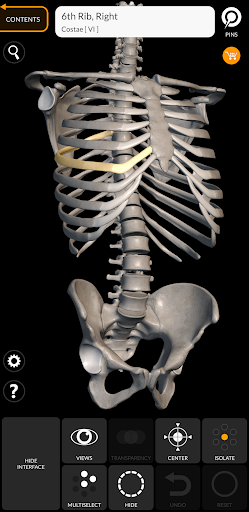

Mỗi xương của bộ xương người đã được tái tạo ở dạng 3D, bạn có thể xoay và phóng to từng mô hình và quan sát chi tiết từ mọi góc độ.

Bằng cách chọn mô hình hoặc ghim, bạn sẽ được hiển thị các thuật ngữ liên quan đến bất kỳ bộ phận giải phẫu cụ thể nào, bạn có thể chọn từ 12 ngôn ngữ và hiển thị các thuật ngữ bằng hai ngôn ngữ cùng lúc.

HÌNH GIẢI PHẪU 3D CÓ ĐỘ CHI TIẾT CAO

• Hệ thống xương

• Mô hình 3D chính xác

• Bề mặt của bộ xương có kết cấu độ phân giải cao lên đến 4K

• Xoay và Phóng to mọi mô hình trong không gian 3D

• Phân chia theo vùng để có hình ảnh rõ ràng và trực tiếp về từng cấu trúc

• Ghim tương tác cho phép trực quan hóa thuật ngữ liên quan đến mọi chi tiết giải phẫu